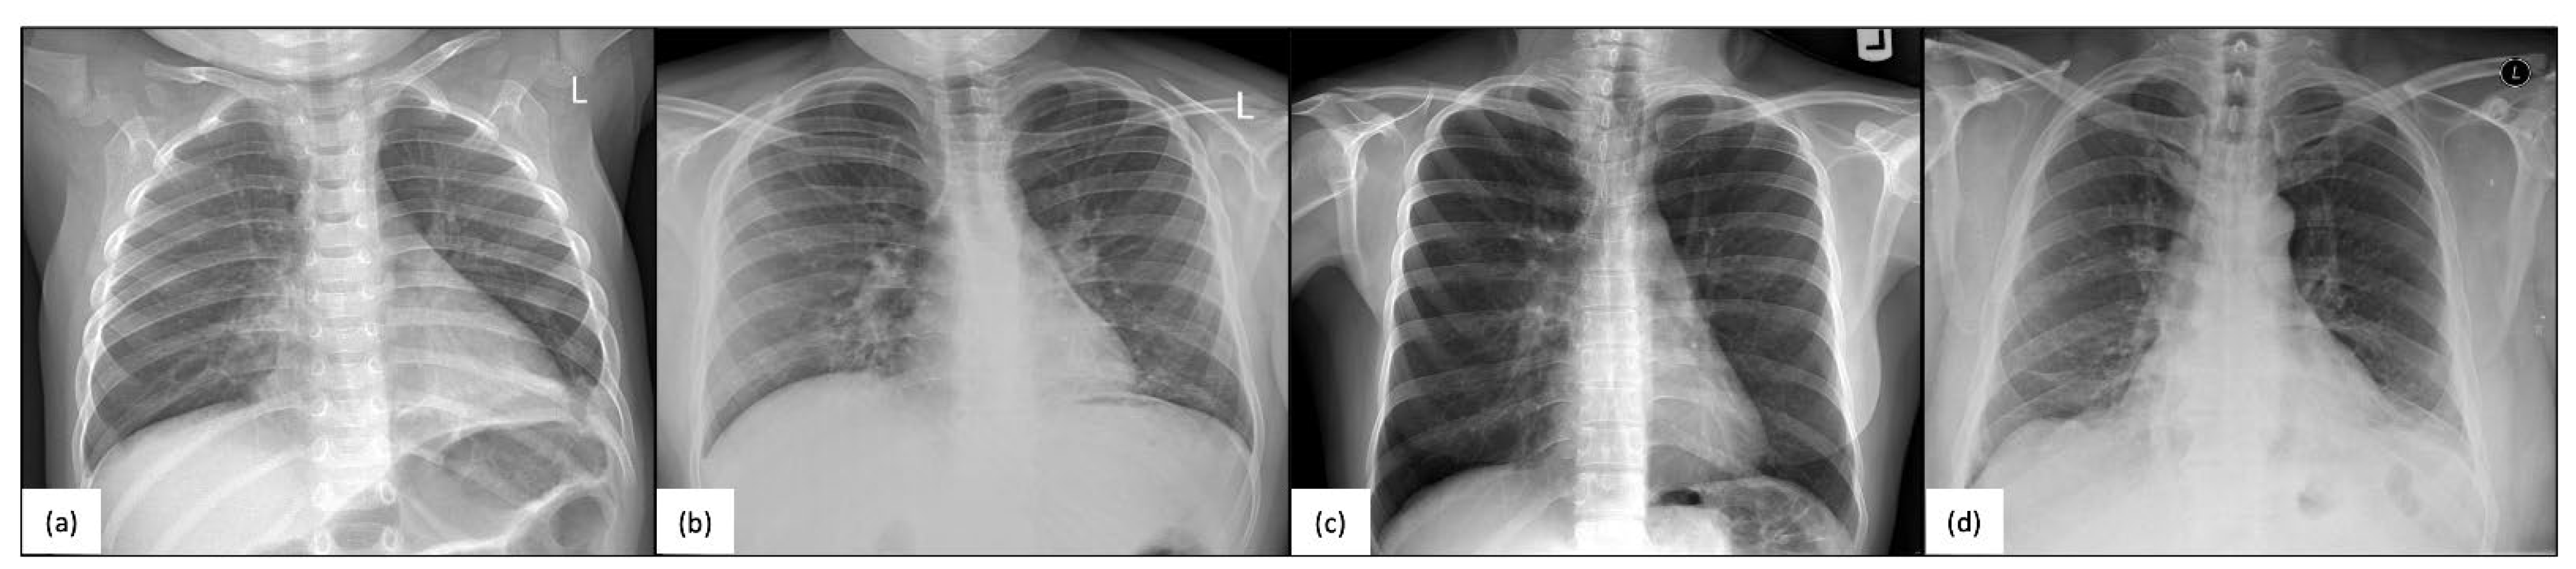

4.1. Pulmonary Disease in Humans with the RSPH4A Mutation